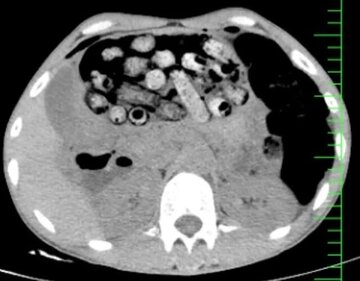

خروج ۹۰ بسته مواد مخدر از معده و روده یک بیمار +عکس

دانشگاه علوم پزشکی البرز از خارج کردن ۹۰ بسته مواد مخدر از معده و روده یک بیمار در کرج خبر…